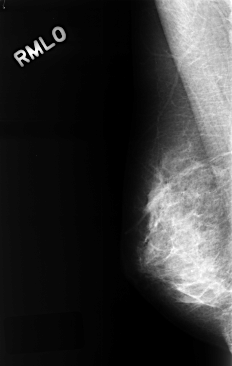

C_0323_1.RIGHT_MLO

RIGHT_CC LINES 4448 PIXELS_PER_LINE 2848 BITS_PER_PIXEL 12 RESOLUTION 50 NON_OVERLAY

RIGHT_MLO LINES 4384 PIXELS_PER_LINE 2784 BITS_PER_PIXEL 12 RESOLUTION 50 NON_OVERLAY